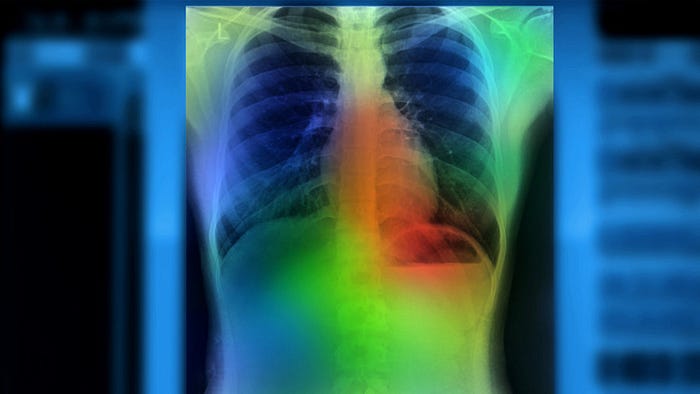

(3) Can AI make medical imaging analysis more efficient and accurate? Qure.ai is one of the most advanced startups deploying AI-powered algorithms for medical imaging. They have specialized algorithms for x-rays, CT scans, and MRIs: the three most common imaging modalities used in hospitals. Their products feature fully automated detection and 3D visualization. And their algorithms are incredibly accurate.

A study involving 1.2 million x-rays and their corresponding radiology reports tested the Qure.ai system and confirmed its accuracy. Similarly, their head CT algorithm has been used for triage of brain bleeds, fractures, and monitoring the progression of traumatic brain injury.